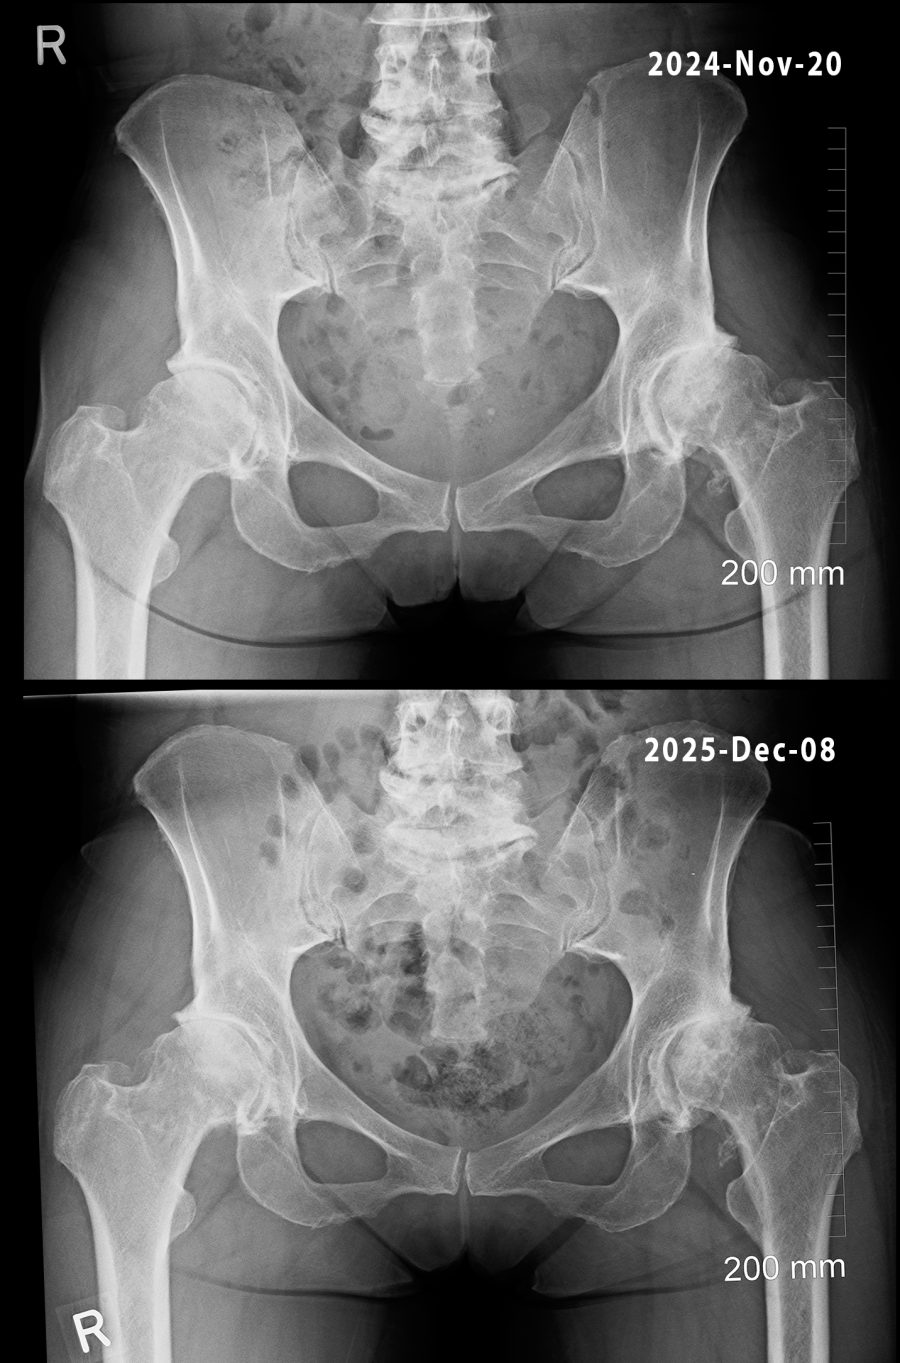

hips.jpg